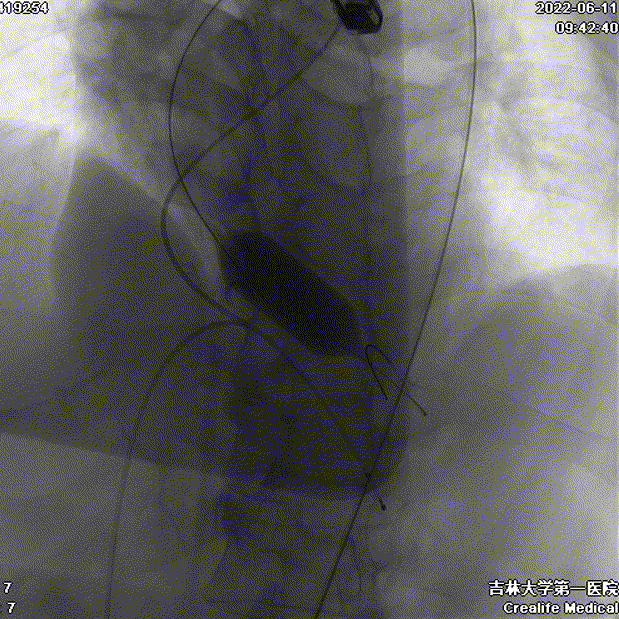

术中影像

主动脉根部造影

瓣膜工作位造影

瓣膜形态良好 位置理想

少量瓣周漏 平均跨瓣压差7mmHg